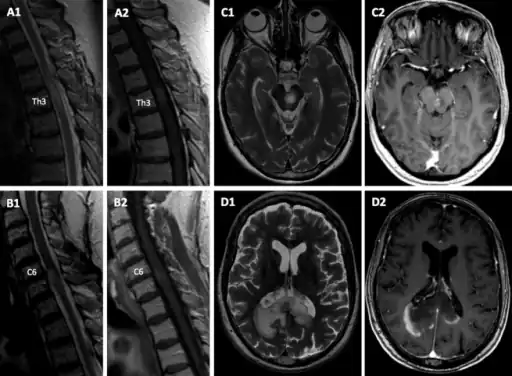

a1,2) sMRI T2- hyperintense lesion on level Th3 with Gd-enhancement on T1w on sagittal sequences b1,2) sMRI new cervical lesion on level C6 with T2 hyperintense signal and rim-enhancing pattern c1,2) cMRI shows a sharply demarcated pontomesencephalic; leopard pattern was noted on T2-weighted sequences with multiple small focal zones d1,2) demarcated confluent tumefactive parieto-occipital lesion across the splenium of the corpus callosum with rim-enhancing pattern